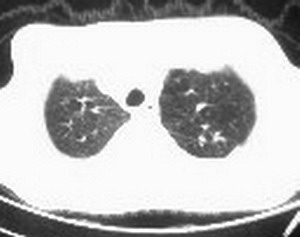

标题: CT6943:[讨论]胸部,M/67Y,体检发现。 [打印本页]

标题: CT6943:[讨论]胸部,M/67Y,体检发现。

ct值约12hu。

ct值约12hu

右肺下叶支气管阻塞,右下叶不张,考虑中心型肺癌伴下叶不张

先考虑:右下肺中心型肺癌伴下叶肺不张、胸腔积液

右肺下叶支气管闭塞,中间段支气管狭窄,下叶不张,胸腔及叶间积液.中心型肺癌伴下叶肺不张.胸腔和叶间积液.

右肺下野后部均匀低密度影,边缘锐利,前缘外突(不支持肺不张),纵隔内未见明显肿大淋巴结,右下肺门结构显示欠清,临床资料太过简单,考虑右侧后胸部包裹性积液。其他待排。建议密切结合临床其他检查。

ct值12,包裹性胸腔积液,